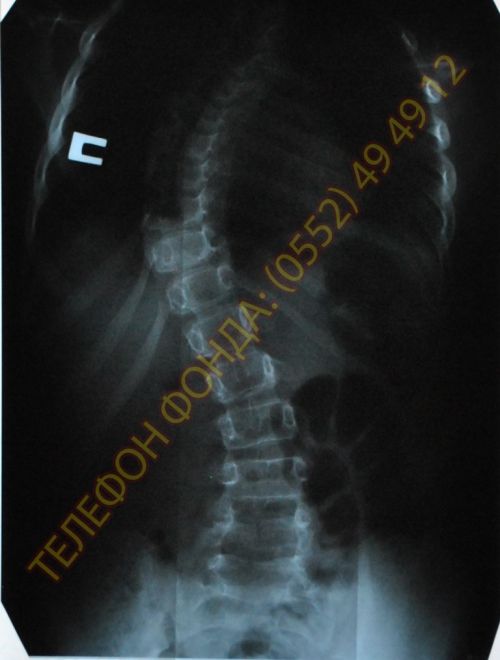

Марине Егоровой нужна неотложная операция. Врачи поставили диагноз: S-образная сколиотическая деформация с левосторонней дугой искривления в шейно-грудном отделе; с правосторонней дугой искривления в грудо-поясничном отделе. Во время операции будут поставлены имплантанты XIA Stryker из титанового сплава для фиксации позвоночника. Стоимость операции и набора имплантантов: 80 000 гривен (8 000 евро). Операция будет проходить в Институте патологии позвоночника и суставов им. проф. М.И. Ситенко в Харькове.